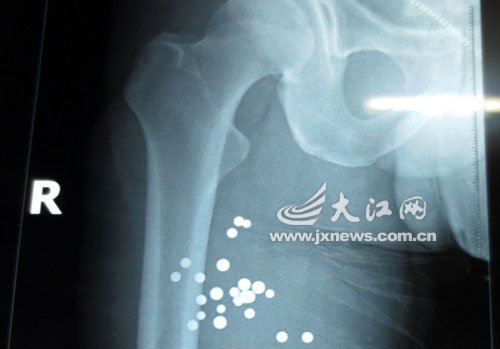

拍片發現鄢先生體內有一大片鋼珠

據武警江西總隊醫院燒傷整形手足外科醫師劉序介紹,鄢先生剛剛被送來時,出現了失血性休克,情況十分危急。經過迅速的清創和拍片后,確定了鄢先生的傷勢:右腹和右腿部位有貫穿傷,通過拍片發現體內有一大片鋼珠,“右腹部位從左上側貫穿到肋骨,兩根肋骨骨折,鋼珠反彈后到達左下側;右腿從前內側到后內側有貫穿傷。”

據劉醫師稱,13時許鄢先生接受手術治療,經過整整四個小時的手術,體內取出了40多粒鋼珠。“大部分彈片已經被取出,還有一小部分有待觀察診治。”在一張白紙上,記者看到了取出的鋼珠,大到青豆大,小到扁豆大,大小不一。